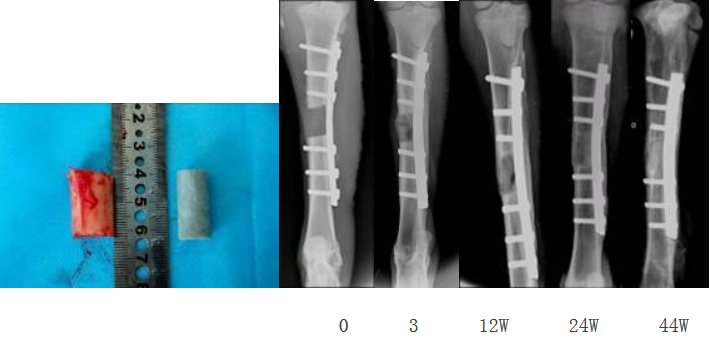

長春應化所科技人員在國家“863計劃”課題的支持下,通過與在生物可吸收導電高分子,羥基磷灰石納米復合材料和電刺激定向誘導組織再生等方面進行了研究,國際上首先將生物可吸收的導電高分子共聚物與電刺激技術相結合應用于骨科修復,開發了電活性智能骨修復材料、骨科固定融合器件和電刺激增強骨再生等新技術,在提高材料的生物降解性、力學性能、成骨生物活性和有效持續控制生長因子基因釋放等方面取得進展。所制備的材料和器件具有良好的生物相容性,達到了國家對植入材料的生物安全性要求。材料的細胞擔載能力明顯提高,具有骨傳導和誘導活性,對骨缺損的愈合能力和愈合質量有明顯提高。課題實施期間申報國家發明專利 14 項,發表 11 篇學術論文,其中5 篇發表在Biomaterials, Biomacromolecules等生物材料領域的國際著名刊物上。該課題完成了相關的動物實驗,顯示了良好的臨床應用前景。